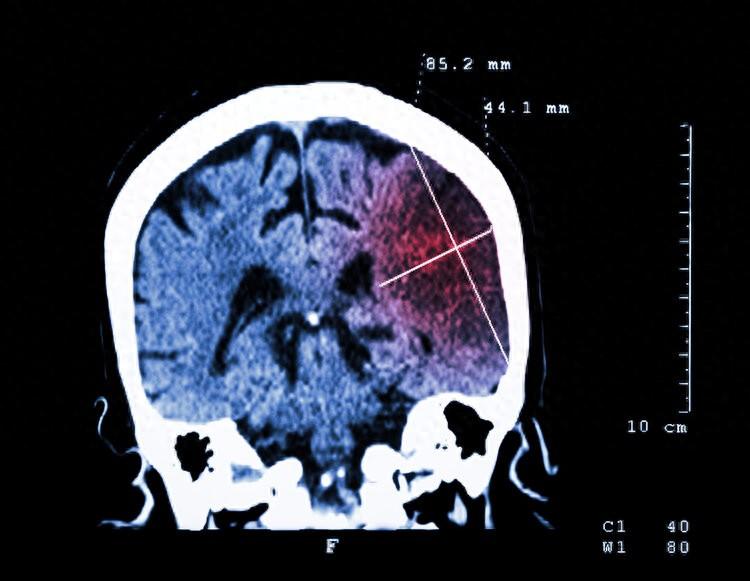

可過了一段時間後,眼睛不但沒有好轉,反而越來越嚴重了,便趕緊讓兒子帶着到了醫院檢查。眼科醫生建議劉叔叔到神經科去看診,經頭顱核磁共振檢查發現是腦梗引發的視覺模糊。

由於劉叔叔右側腦部的腦梗破壞了視覺形成通路,從而引發了視物模糊,好在經過醫院的積極治療,劉叔叔左眼視力在不斷恢復。

腦卒中,俗稱中風,是由於腦部血管堵塞或破裂引發了腦組織損傷的疾病。腦卒中致殘率和致死率都很高,據統計我國每年約有220萬人因腦卒中而致殘。

腦卒中可以分爲缺血性腦卒中(腦梗)和出血性腦卒中(腦出血)兩大類型,其中腦梗約佔全部腦卒中的70%。近年來,有種說法稱我國腦梗患病人數之所以這麼龐大,與葉酸喫太少有關。